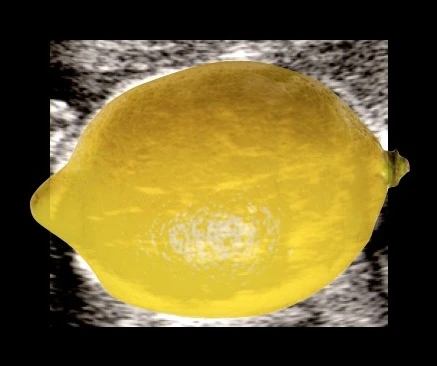

Sinal do limão: os ossos frontais do crânio assumem uma concavidade bilateral, dando ao crânio uma silhueta em forma de limão na imagem axial. Presente em 53 a 100% dos casos no segundo trimestre, mas tende a desaparecer após 24 semanas à medida que os ossos do crânio se ossificam.

Sinal do limão no ultrassom — crânio fetal com formato de limão característico da mielomeningocele